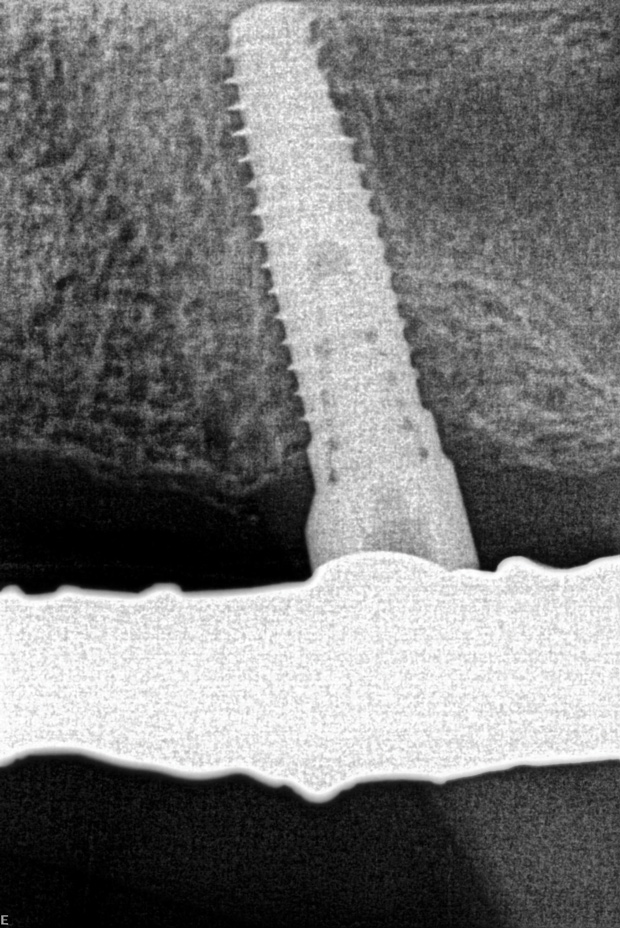

When the patient presented in March 2016, the definitive hybrid (fixed-removable) prosthesis was removed, revealing radiographic and clinical evidence of a failed implant in the area of tooth No. 13 (Figure 2). The patient returned in May, at which time the maxillary prosthesis was removed and the implant at site No. 13 explanted. The site was curetted, and a wider-diameter implant was immediately inserted into the explanted site, producing excellent primary stability. A healing abutment was then placed on the new implant, and the existing framework was modified, allowing the healing abutment to provide an occlusal stop on the underside of the framework (Figure 3 and Figure 4).

Fig 2. Preoperative radiograph revealing the failing implant at No. 13 that would be explanted; then the site would be curetted and a new, wider-diameter implant placed.

Figure 2